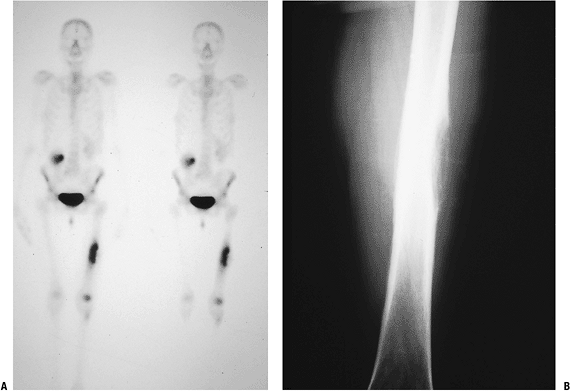

P.236![]() Figure 8-4 (A) Figure 8-4 (A)

An isolated left distal femoral bone lesion in an elderly woman without

Biopsy showed metastatic adenocarcinoma. (B) Computed tomography scan of the lung revealed a mediastinal mass consistent with a lung carcinoma primary. Figure 8-5 A lytic, relatively well-defined metastatic lesion of the right humerus in a patient with renal cell carcinoma. Figure 8-5 A lytic, relatively well-defined metastatic lesion of the right humerus in a patient with renal cell carcinoma.![]() Figure 8-6 A pelvic radiograph shows typical blastic metastases from prostate cancer.P.237 Figure 8-6 A pelvic radiograph shows typical blastic metastases from prostate cancer.P.237 Figure 8-7 Figure 8-7